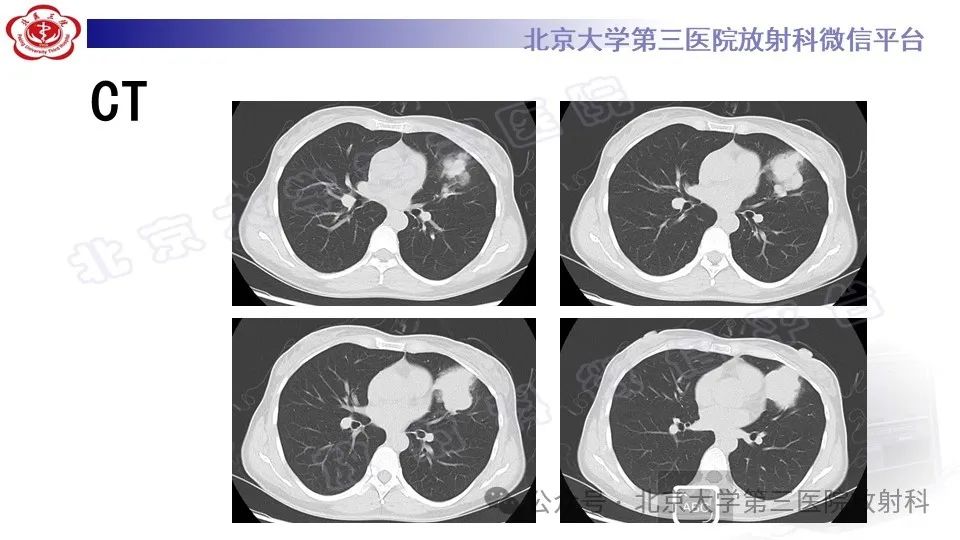

肺肉瘤样癌1例|今日病例

来源:北京大学第三医院放射科